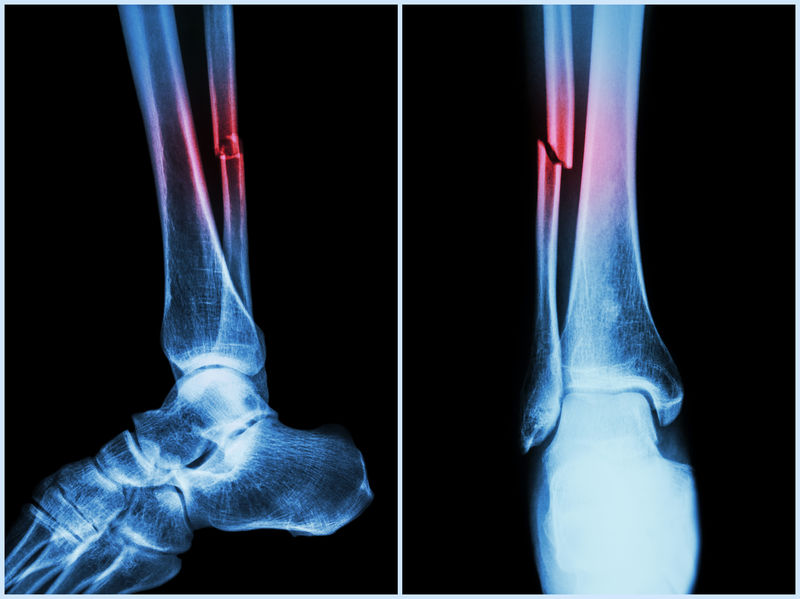

Objawy towarzyszące złamaniom są uzależnione od umiejscowienia i rozległości urazu. Złamania kości długich (piszczelowej, udowej, ramiennej) są niebezpieczne i ich rozpoznanie zazwyczaj nie stanowi problemu, choćby ze względu na silny ból odczuwany przez chorego. W przypadku mniejszych złamań symptomy nie zawsze są tak charakterystyczne.